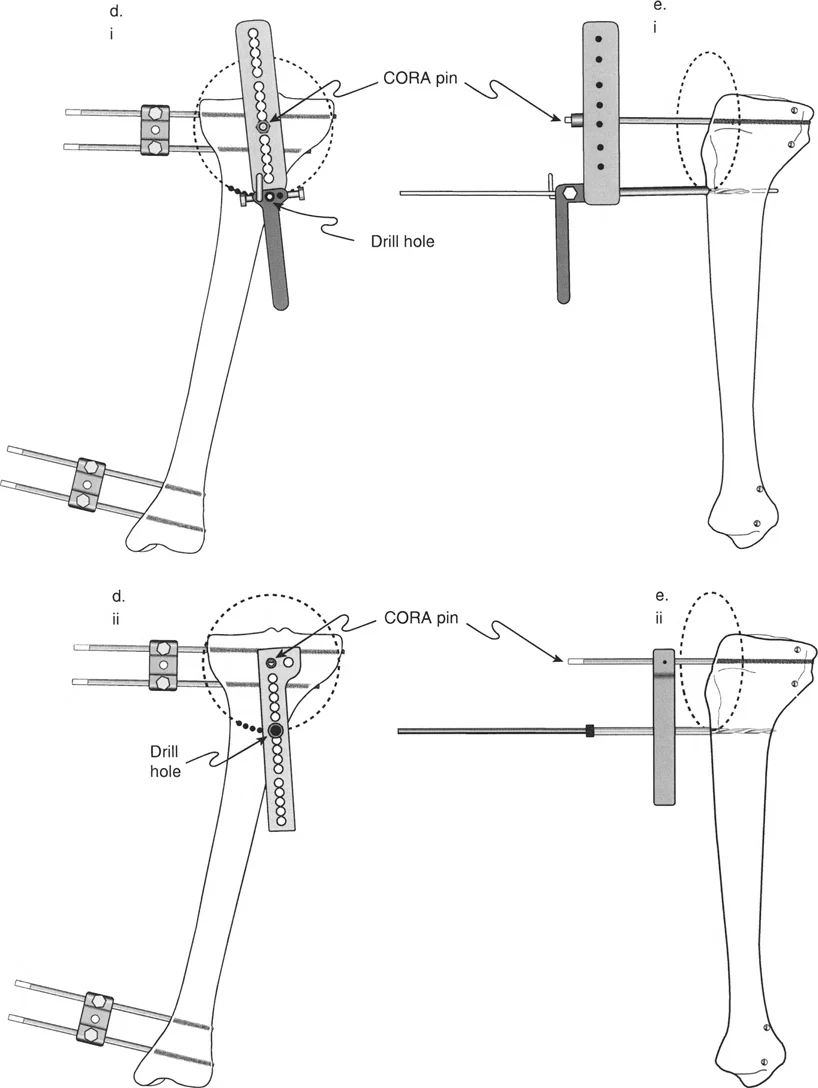

تساعد هذه الزوايا الأستاذ الدكتور محمد هطيف على تحديد ما إذا كان التشوه في الركبة مصدره عظم الفخذ أو عظم الساق، وهو أمر حاسم لتخطيط العمليات الجراحية مثل قطع العظم (Osteotomy) أو استبدال مفصل الركبة.